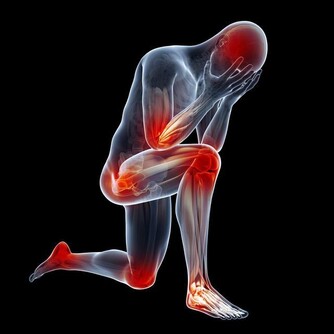

5. 沒有計劃的非科學鍛煉

鍛煉是一個循序漸進的過程,想要通過深蹲練就翹臀,應該逐漸增加運動量;而不是某天心血來潮,連續做一百個蹲起。突然加大運動量,或是熱身運動不到位,都會對肌肉組織造成不小的壓力,甚至是誘發痔瘡。條件允許時,最好能請專業人士為自己量身打造健身計劃,在專人看護與輔導下使用健身器械。醫生提醒:痔瘡患者的數量龐大,但也不要因為這類疾病比較普遍而不去看醫生。